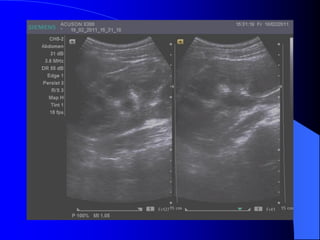

* Siãu ám: Hçnh cáöu, räùng ám, tàng ám sau, båì âãöu

khäng tháúy roî thaình nang. (Nãúu âuí caïc tiãu

chuáøn trãn, âäü chênh xaïc laì 100%.)

Trãn siãu ám laì khäúi räùng ám, tàng

ám sau, thaình moíng, åí xoang tháûn.

Phán biãût våïi æï næåïc âaìi bãø tháûn, åí âáy

caïc nang caûnh bãø tháûn khäng thäng

nhau.